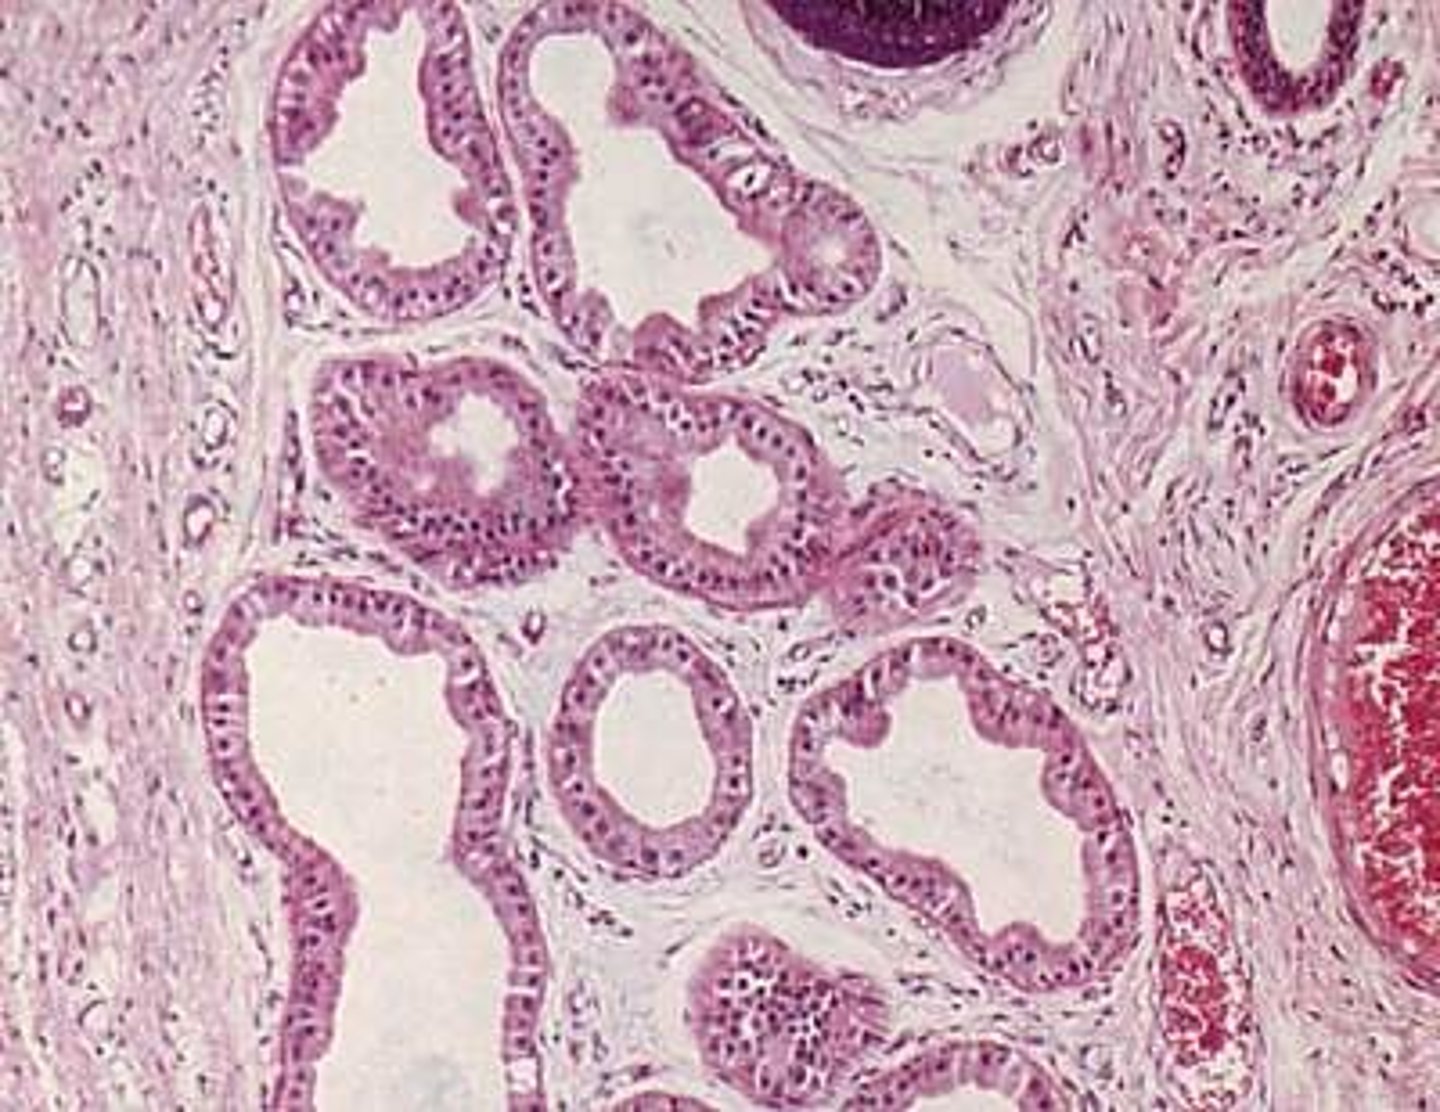

Epidermis

Outer layer of skin

stratum corneum

outermost layer of epidermis

stratum lucidum

Clear, transparent layer of the epidermis under the stratum corneum.

stratum granulosum

a layer of the epidermis that marks the transition between the deeper, metabolically active strata and the dead cells of the more superficial strata

stratum spinosum

stratum basale

the deepest layer of the epidermis consisting of stem cells capable of undergoing cell division to form new cells